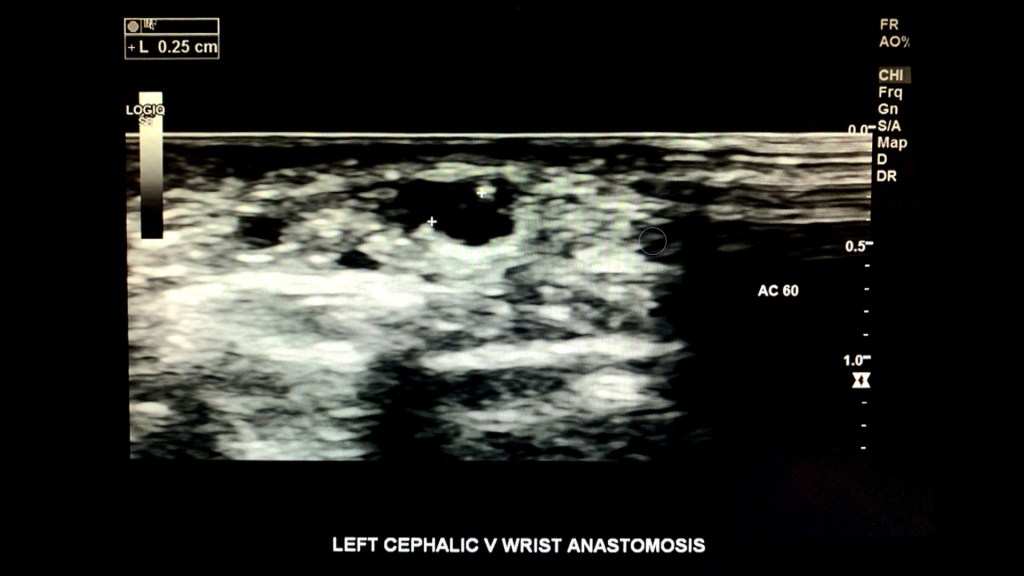

Make sure to measure the size of the anastomosis before completing the exam.